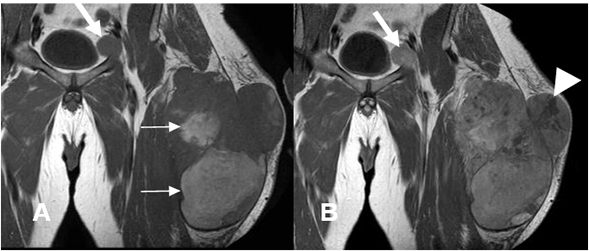

Fig 110 A. Sarcoma pleomórfico indiferenciado.

A: RM axial en T1. Lesión hipointensa y heterogénea de tejidos blandos y crecimiento agresivo, en el compartimiento posterior de la pierna.

B: RM axial en T2. Imagen heterogénea con área de señal intermedia por contenido fibroso (Flecha delgada) y otra hiperintensa, por necrosis. (Flecha gruesa).

Fig 110 C. Sarcoma pleomórfico indiferenciado.

A: RM coronal en T1 simple y B: RM coronal en T1 con contraste. Igual paciente anterior. Lesión tumoral con zonas hiperintensas en la fase simple, por sangrado subagudo. (Flechas delgadas). Un gran porcentaje del tumor realza con el contraste, pero se identifican zonas hipointensas, por necrosis. (Punta de flecha). La adenopatía inguinal izquierda, también realza con el contraste. (Flecha gruesa).